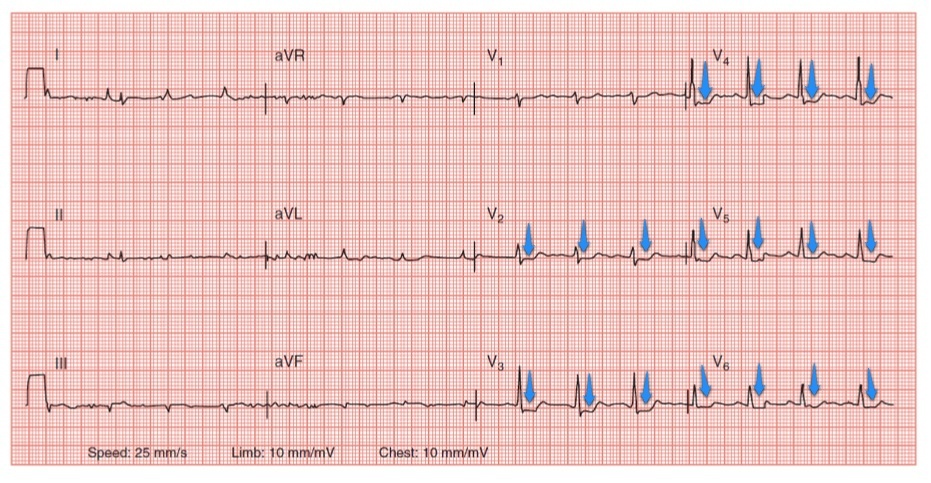

El electrocardiograma☤ tiene un patrón típico en el infarto que, en ocasiones especiales☤, puede modificarse:

- Onda T invertida por la isquemia.

- Elevación del ST por daño agudo o reciente.

- Aparición de onda Q patológica☤ por necrosis.

- Elevación persistente del ST.

Cursa con ascenso del ST en V3R y V4R, e insuficiencia cardíaca☤.